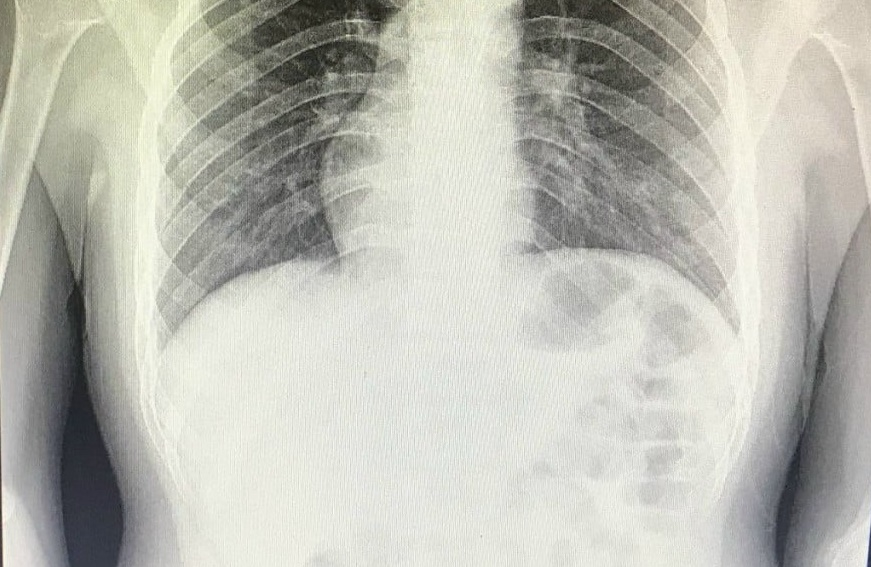

Hình ảnh phim chụp x-quang của bệnh nhân với phủ tạng nằm bên phải.

Ngay sau khi tiếp nhận thông tin, bệnh nhân được các bác sĩ thăm khám và làm các chỉ định cận lâm sàng cần thiết để xác định nguyên nhân gây đau như siêu âm ổ bụng, chụp x-quang, xét nghiệm máu. Bệnh nhân được chẩn đoán viêm ruột thừa, hình ảnh trái tim trong lồng ngực ở bên phải, vị trí đảo ngược so với người bình thường.